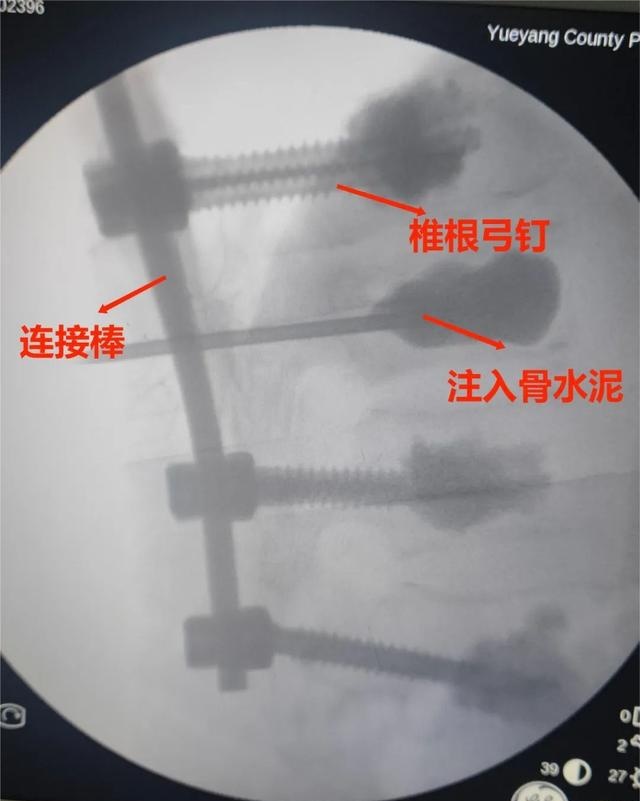

经神经脊柱外科多次术前讨论,在岳阳市人民医院钟炯彪主任医师指导下,决定为患者实施经皮骨水泥螺钉+伤椎椎体成形术。

术中、术后影像(8钉2棒)

椎弓根螺钉置入➪螺钉周围骨水泥强化(增强螺钉把持力及稳定性)➪钉棒系统进行伤椎复位并固定➪伤椎内骨水泥强化。